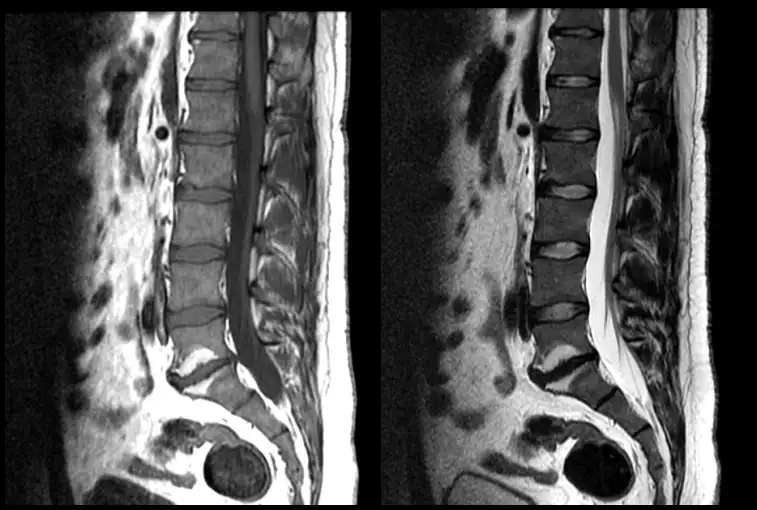

Zmiany Modic to wynik badania rezonans magnetyczny (MRI), który często pojawia się w opisach kręgosłupa osób z przewlekłym bólem pleców. Mogą świadczyć o procesach zapalnych, zwyrodnieniowych i przebudowie trzonów kręgowych, a ich obecność może wiązać się z nasileniem dolegliwości bólowych. W tym wpisie wyjaśniamy, czym są zmiany Modic, jak je rozpoznać, jakie dają objawy i jak wygląda ich leczenie oraz rehabilitacja.